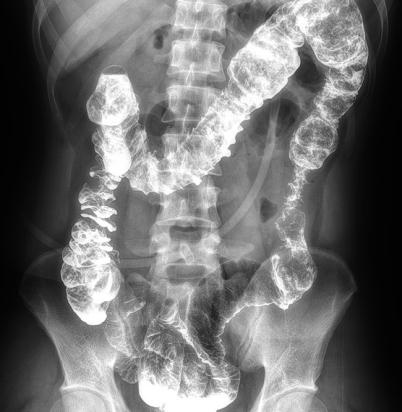

多功能動態平板DR,采用U型臂結構,具有靜態DR攝影、數字透視、數字造影和可視化攝影的功能。

電動旋轉內平衡結構,可實現快捷擺位,滿足特殊體位的靜態與動態檢查。